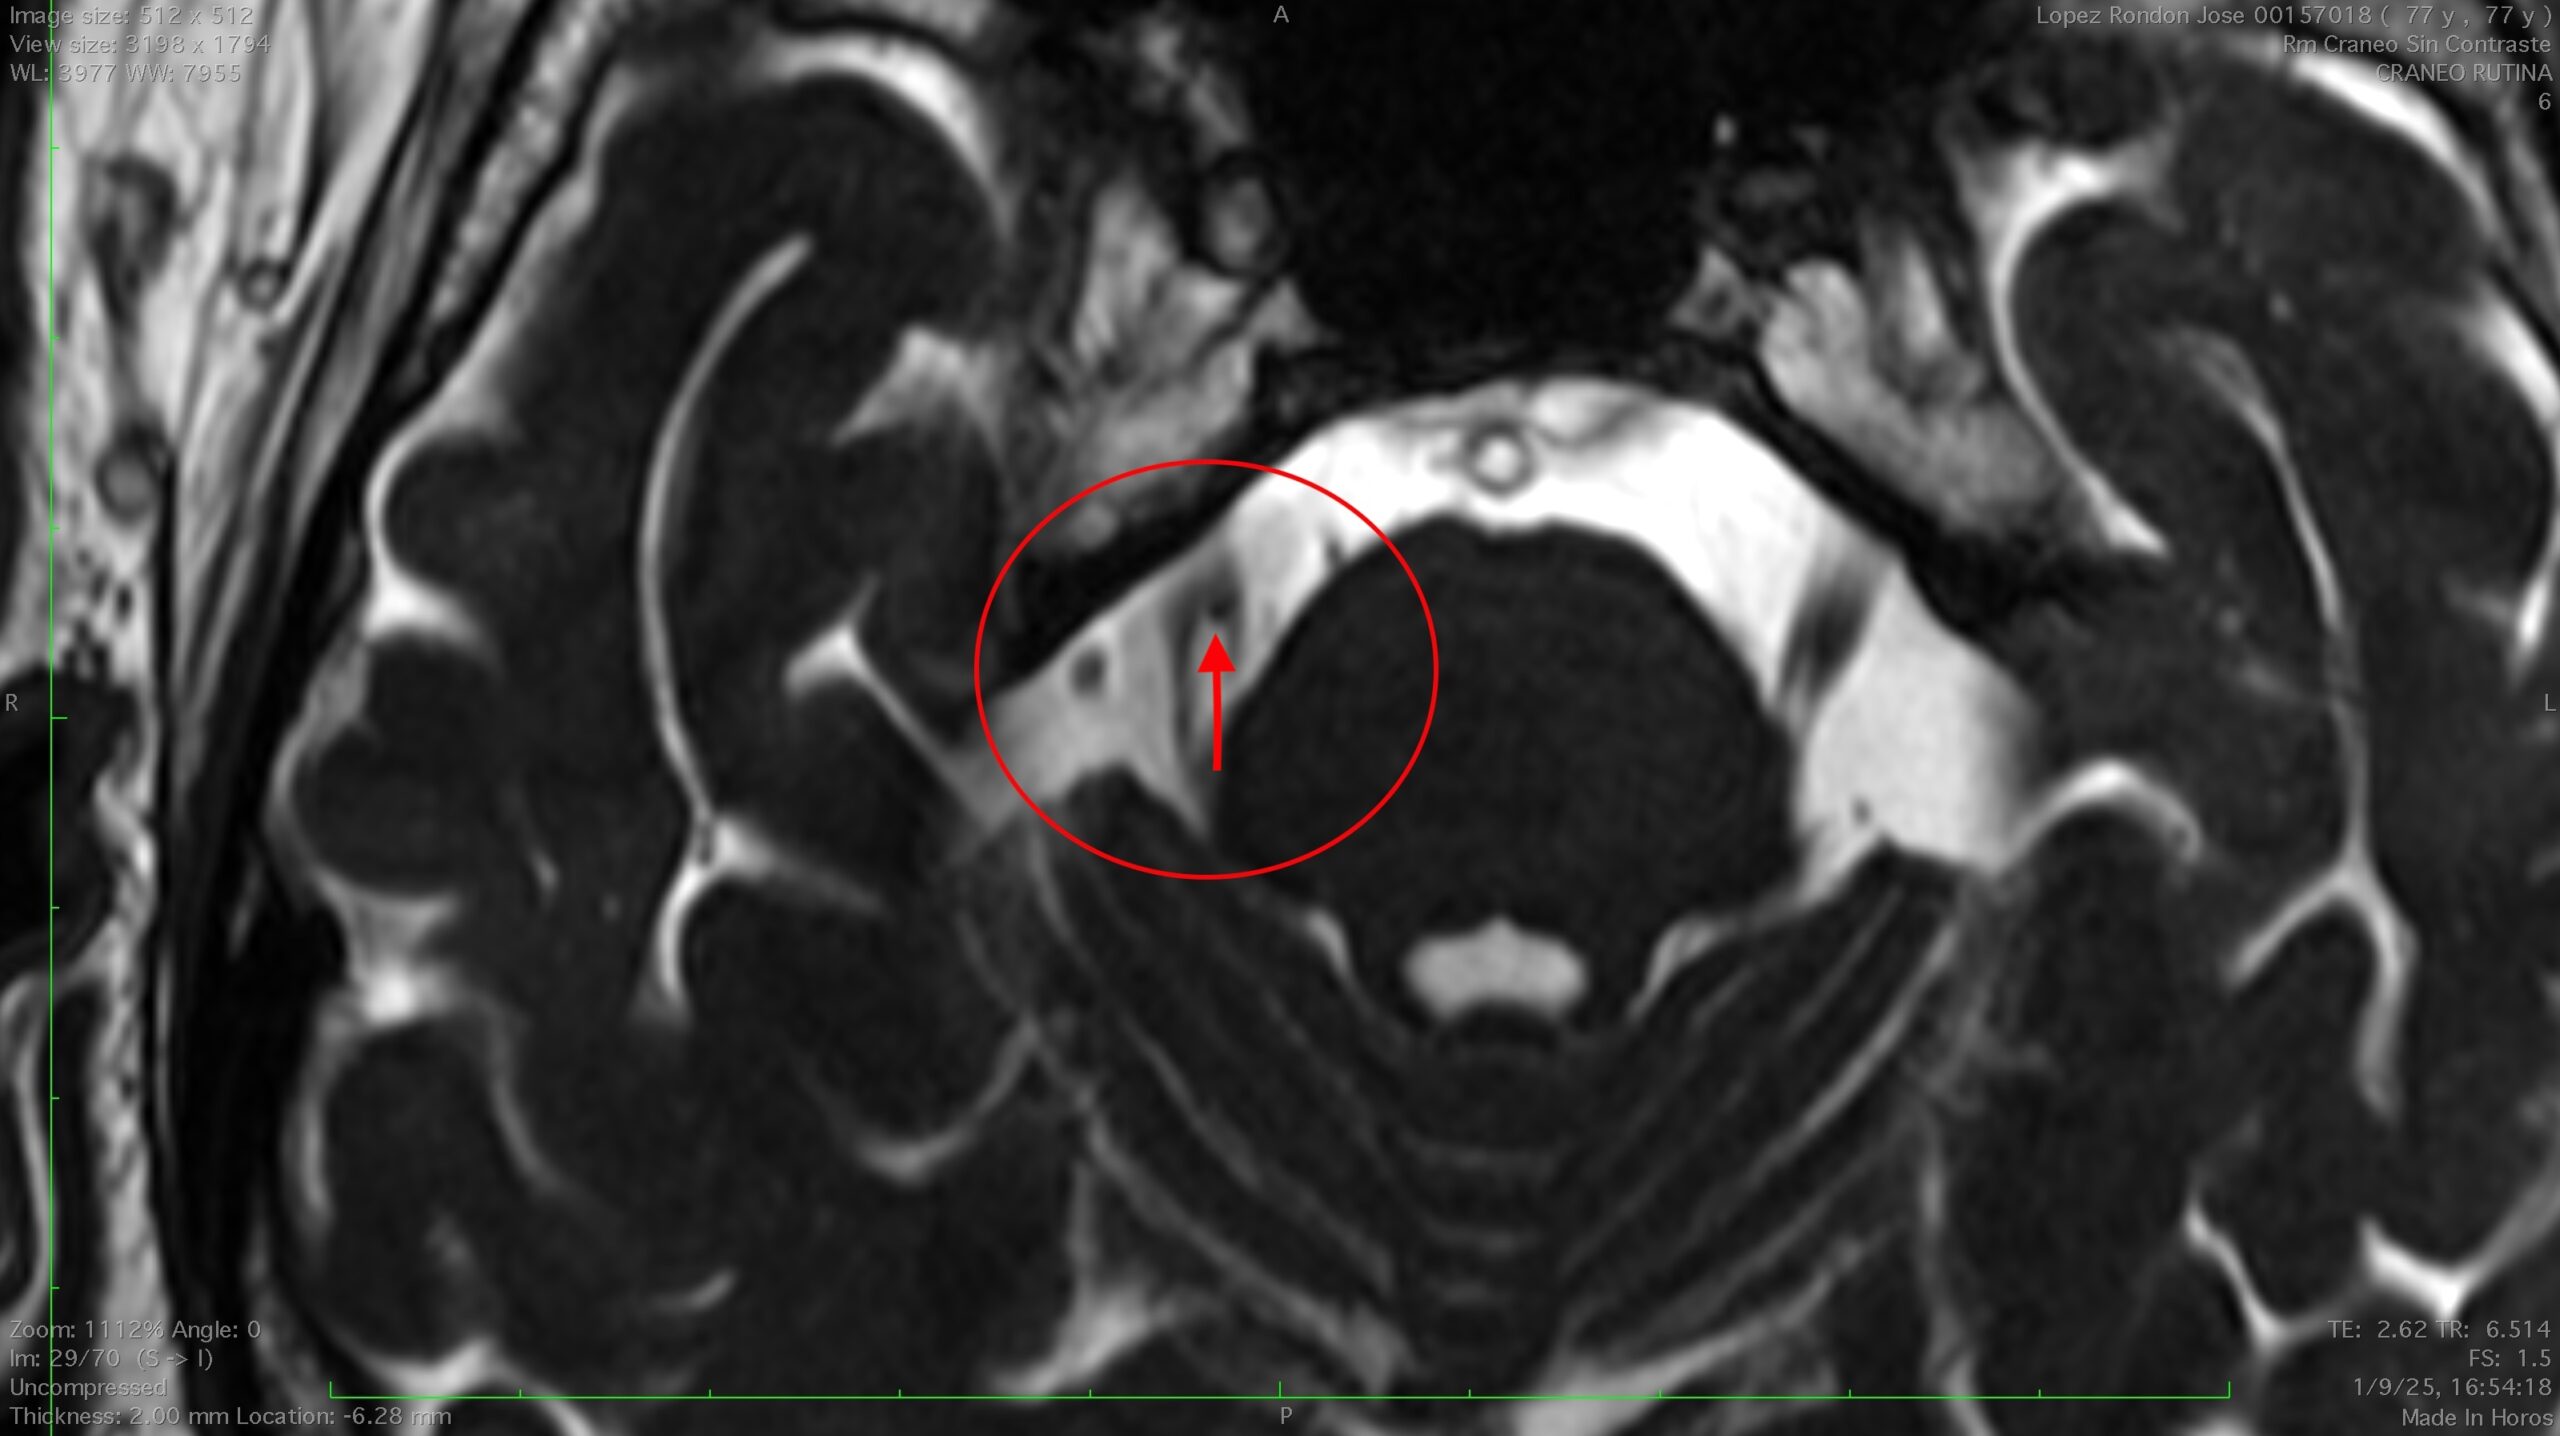

Cuando los tratamientos farmacológicos no son efectivos, la descompresión neurovascular se presenta como la opción quirúrgica más eficaz. Esta técnica consiste en aliviar la presión ejercida por una arteria o vena sobre el nervio trigémino, responsable de desencadenar los episodios de dolor. Es espacialmente indicado en pacientes por debajo de los 70 años y sin patologías graves asociadas.

Cuando demostramos que existe una arteria en contacto con el Trigémino podemos casi asegurar la resolución del dolor tras la intervención, con una tasa de resolución de la neuralgia de mas del 98%, esto se puede valorar con RNM previo a la cirugía.